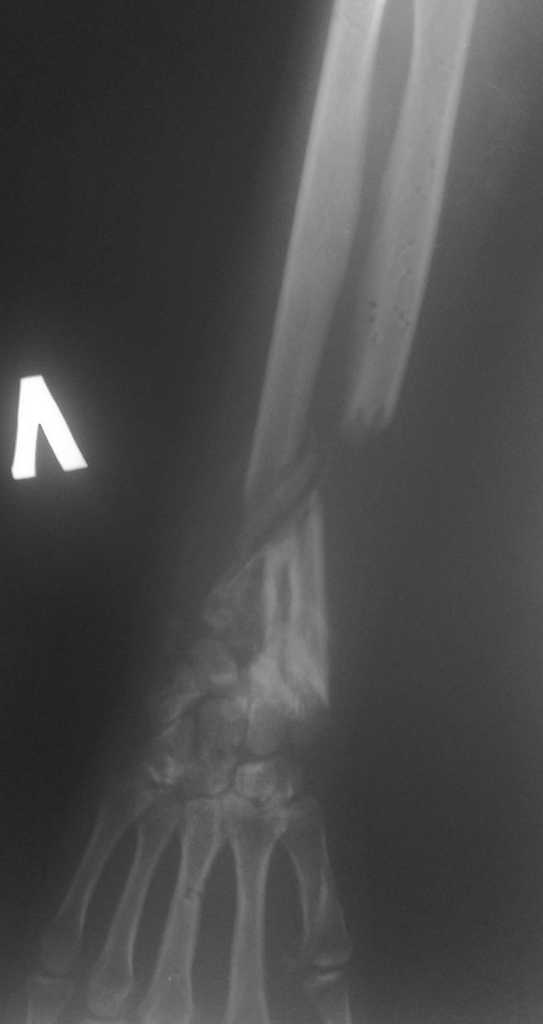

Имеется постттравматический дефект дистальных отделов костей левого предплечья.

Больная Д. 30 лет плучила травму 12.07.09г, пассажир скутера - тяжелая сочетанная травма брюшной полости и конечностей, гемоперитониум, закрытый перелом н\3 ЛЕВОГО БЕДРА, открытый перелом н/3 левого предплечья с дефектом обеих костей, рана голени. С момента травмы перелом предплечья был фиксирован анкерно-спицевым апаратом, проводилось лечение других сегментов. В настоящий момент АВФ демонтирован, имеется следующая рентгенологическая картина (см. приложение), имеется дефект обеих костей и суставных поверхностей. Коллеги подскажите варианты лечения в данном случае ?!

Уважаемый коллега! В данном случае остается одно - формирование артродеза лучезапястного сустава в положении полусупинации (функциональном для левой руки)и восстановление лучевой кости. Труднее это выполнить. На мой взгляд, если нет концевого остеомиелита и трофических язв конечности, можно произвести остеосинтез пластиной с угловой стабильностью лучевой кости с пластикой дефекта аутокостью из подвздошной кости и из дистального фрагмента, если будет необходима резекция выступающего в ладонную сторону отломка. Лучше, если удасться адаптировать положение кисти (устранить тыльное смещение) с минимальной резекцией, освежив поверхности костей запястья и дисальный конец дистального отломка луча. Если есть инфекция - билокальный остеосинтез луча по Илизарову.